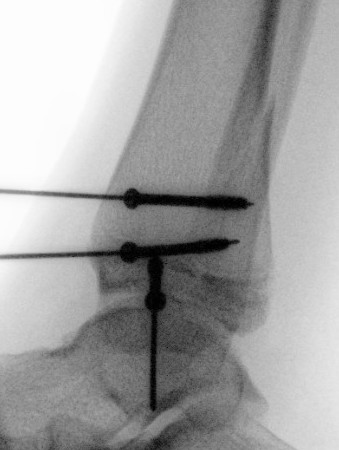

Xray

AP xray: Salter-Harris type III / Tillaux

Lateral xray: Salter-Harris Type II

CT

Coronal images: Salter-Harris type III

Sagittal images: Salter-Harris type II

Axial images: 3 point star